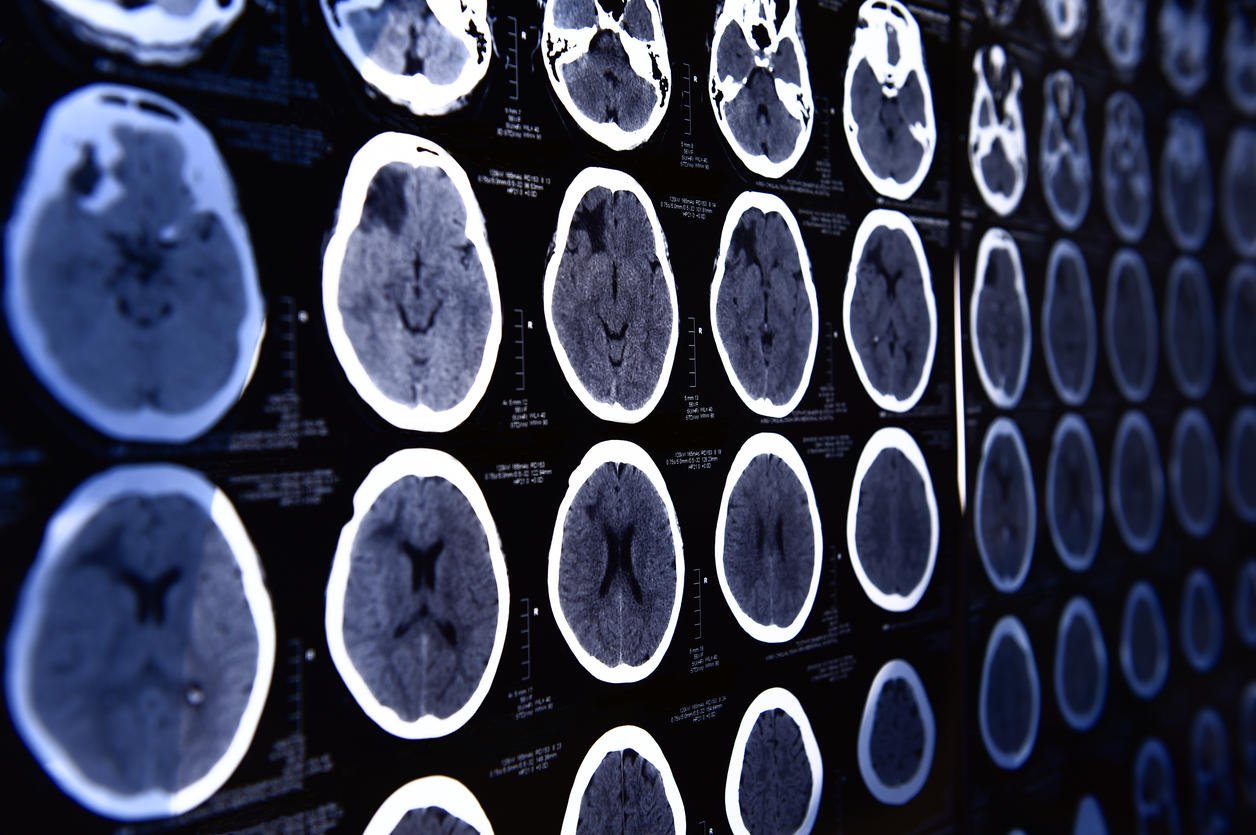

images from a computerized tomography of the brain

Istock